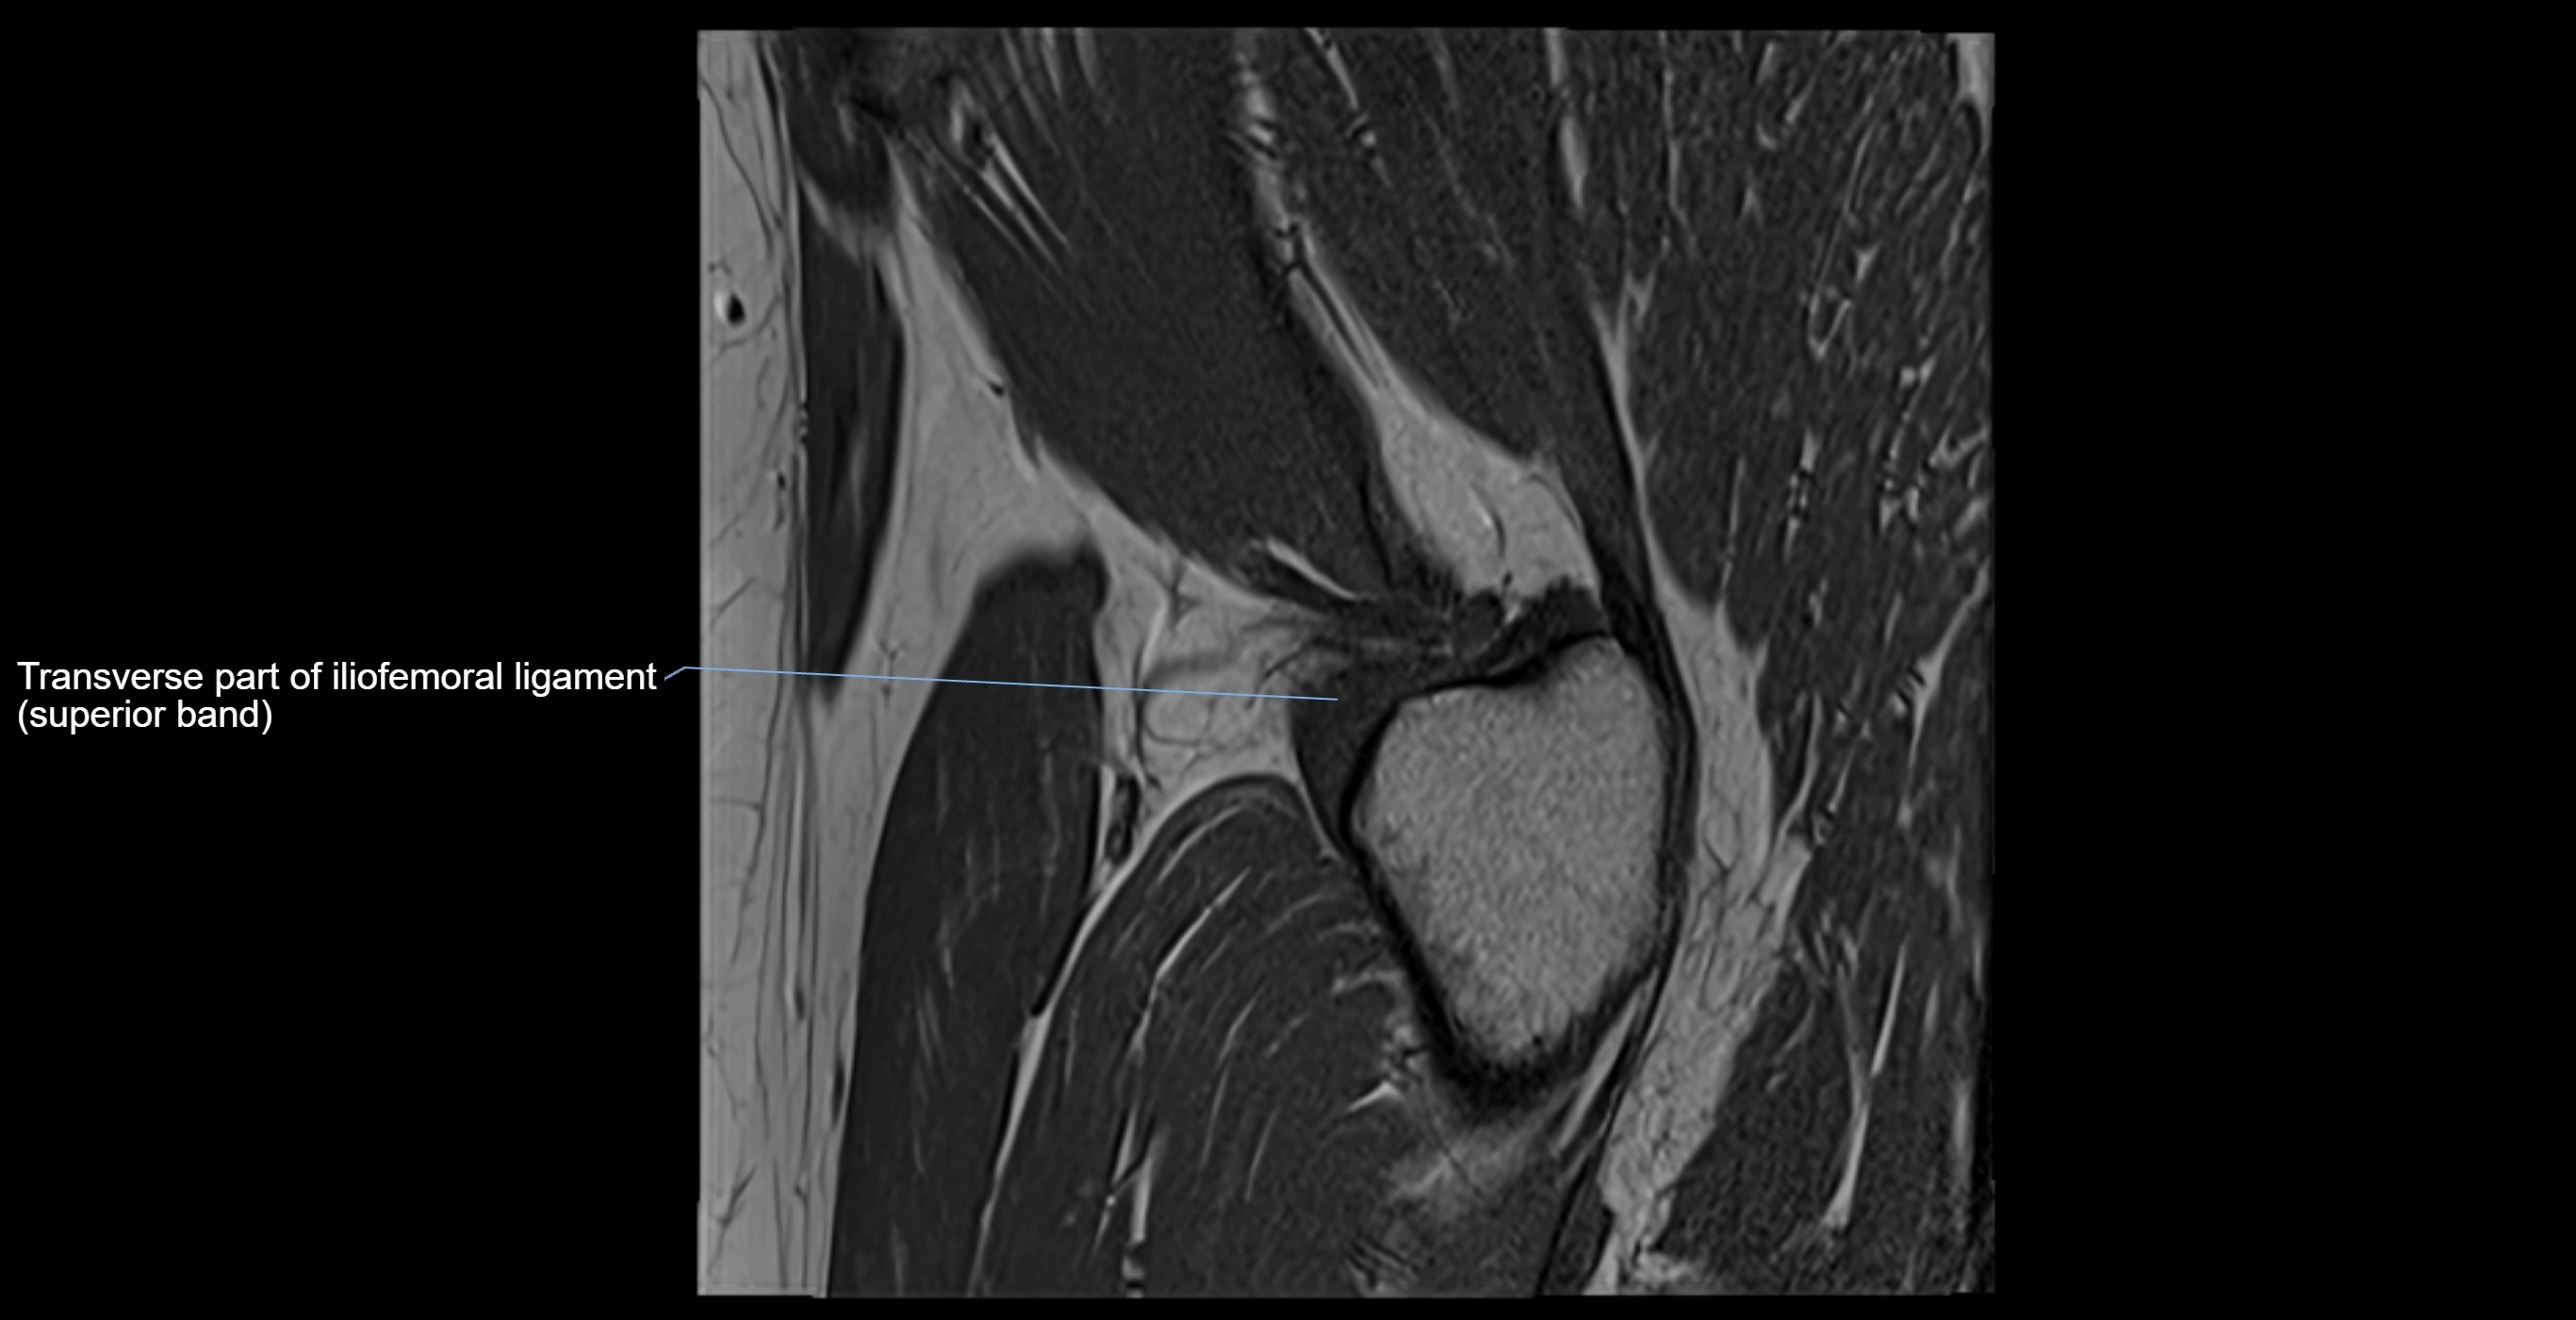

The acetabular labrum is a fibrocartilaginous ring that surrounds the rim of the acetabulum in the hip joint. It deepens the hip socket, increases joint stability, and maintains a suction seal that preserves negative intra-articular pressure. Structurally, the labrum transitions from hyaline cartilage of the acetabulum to dense fibrocartilage at its free edge.

It is triangular in cross-section, with its base attached to the acetabular rim and its apex projecting toward the femoral head. The labrum is most robust superiorly and anteriorly, where load bearing is greatest, and relatively thinner inferiorly.

Structure and Relations

MRI Appearance

T2-weighted images:

• Labrum: low signal intensity (dark)

• Joint fluid: bright, making labral tears visible as fluid extending into or around labrum

MRI image

image